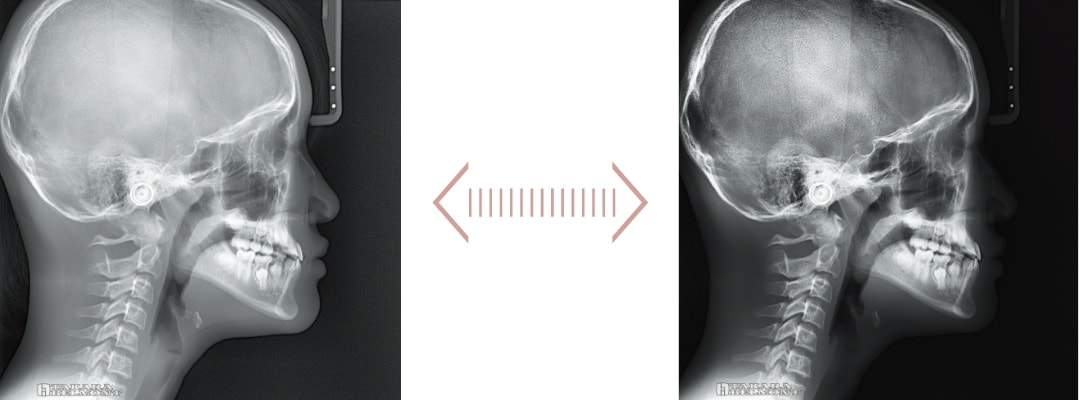

鮮明なセファロ画像を ワンショット撮影で

位置付け時のカメラスカウト機能で、撮影範囲を事前に確認。

0.5秒のワンショット撮影で、ブレの少ない鮮明なセファロ画像が取得できます。

セファロ撮影エリアを事前に確認できるカメラスカウト

位置付け時、X線管部に取り付けられたカメラ画像から、撮影範囲をタッチパネルで確認できます。

鮮明なセファロ画像を

0.5秒のワンショット撮影

最大管電圧100kV(最大管電流9mA)、0.5秒のワンショット撮影で、ブレによる影響を抑えた鮮明な画像が取得できます。

セファロ再構成

撮影後必要な時に、軟組織を強調、硬組織を強調した画像への再構成が可能です。

撮影モード(LA・PA・手根骨)ごとに、デフォルト設定できます。